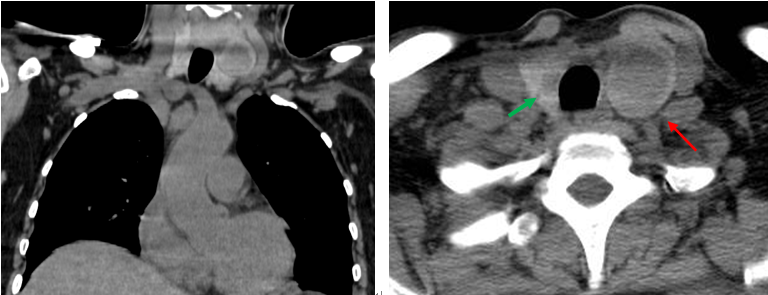

患者同期甲狀腺CT平掃檢查所見:

甲狀腺形態增大,雙葉見類圓形低密度影,大小分別為2.4×2.9cm(左,紅箭),0.7×1.1cm(右,綠箭)。